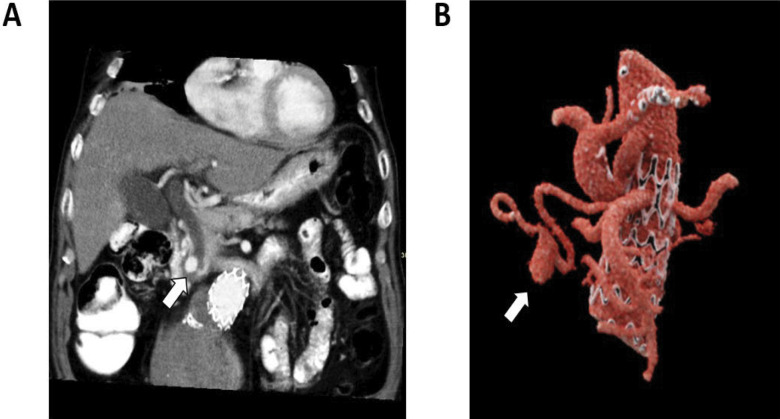

Hepatic artery aneurysms (HAAs) are rare vascular malformations that can arise from atherosclerosis, trauma, or iatrogenic injury. HAAs can be symptomatic and lead to serious complications. We present the case of a patient with painless jaundice caused by obstruction of the distal common bile duct by a HAA on a replaced right hepatic artery. This was further complicated with cholangitis. After endovascular stenting of the aneurysm, cholestasis decreased. Learning point: Hepatic artery aneurysms can cause common bile duct obstruction resulting in cholestasis.